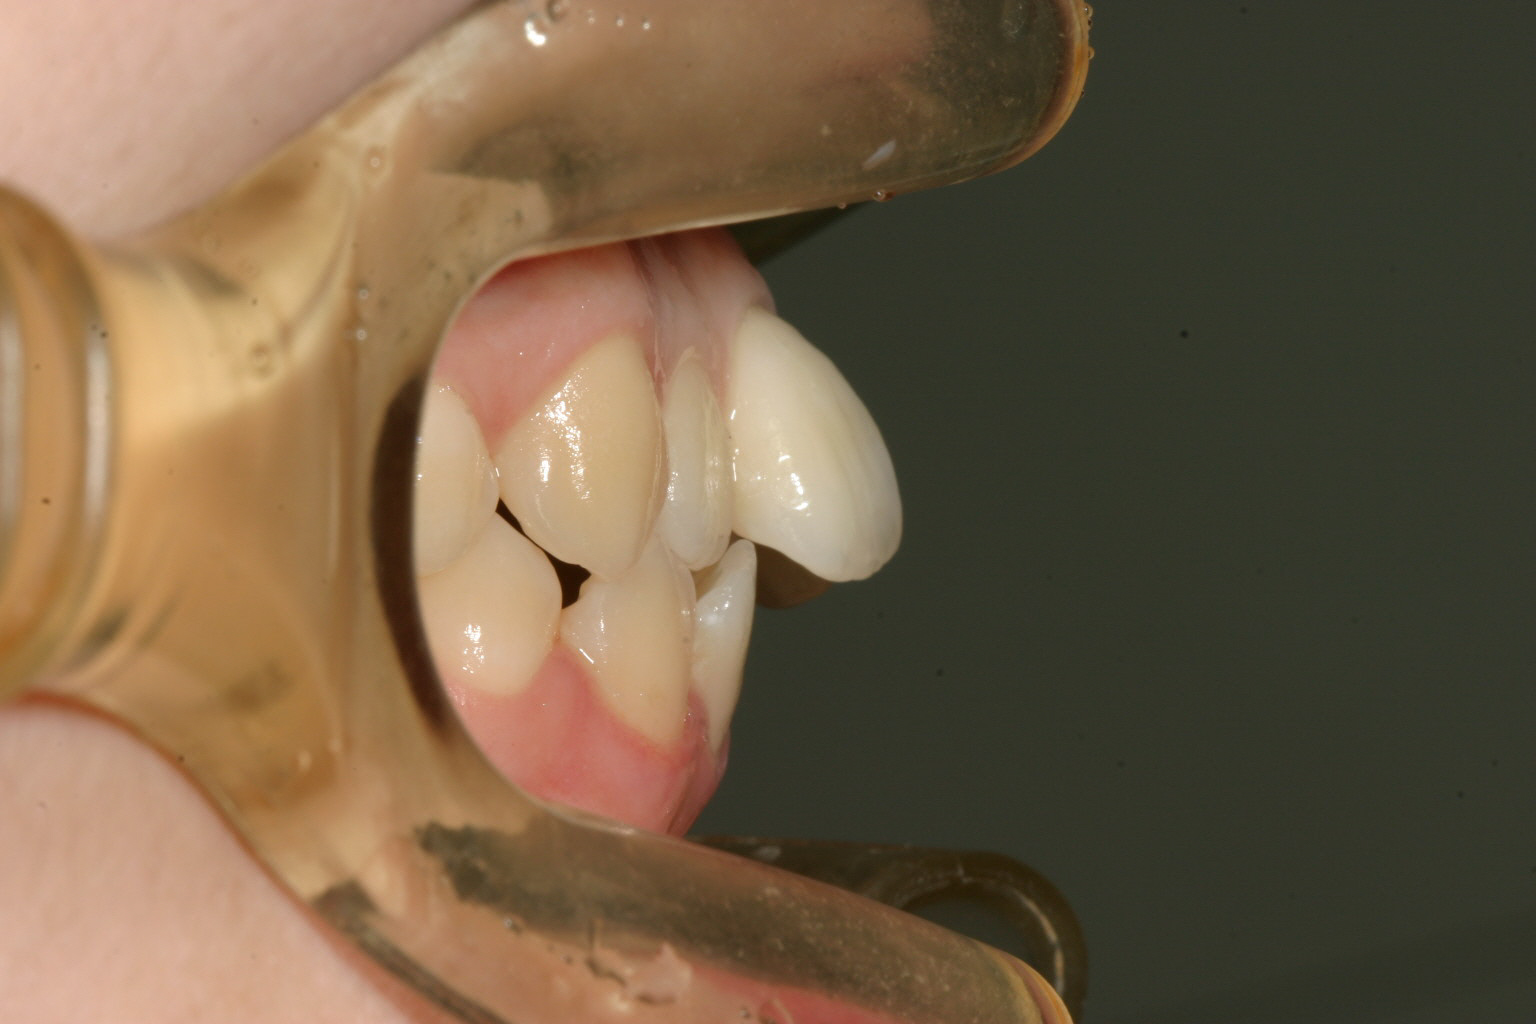

前歯が飛び出てガタガタしてますね。

アーチがV字型な為に前歯が上手く並ばずガタガタしています。

横から見ると上の前歯が突出していますね。